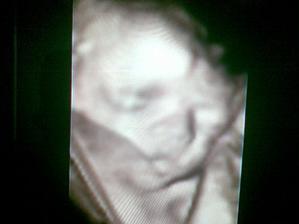

24.2. 4D UZ, definitivně se nám potvrdil chlapeček(Dominik, Michal nebo David), ale ukazovat se nám moc nechtěl 🙂